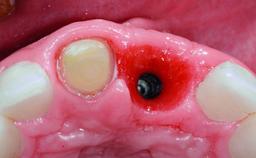

Replacement of a Failing Upper Right Central Incisor, Ridge Preservation and Late Placement of a NC Bone Level Implant

A 30-year-old patient presented at our clinic with a chief complaint of pain in her endodontically treated right maxillary central incisor (tooth 11) with a post-and-core and a fixed single crown. She had a very high lip line, a medium to thin soft-tissue phenotype, and a medium scalloped gingival contour. She also had high esthetic expectations because of her young age and beautiful smile. However, her expectations were realistic and she understood the risks of the treatment. At the initial clinical examination there was a slight mobility of tooth 11; no fistula was observed. The patient also had a single crown on the adjacent tooth 21. Both restorations were old and esthetically deficient. A digital periapical radiograph showed a very small periapical radiolucency, a thick intraradicular post, and no separation between root fragments.